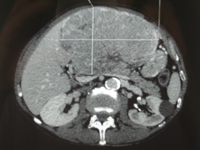

Polykystose hépatique